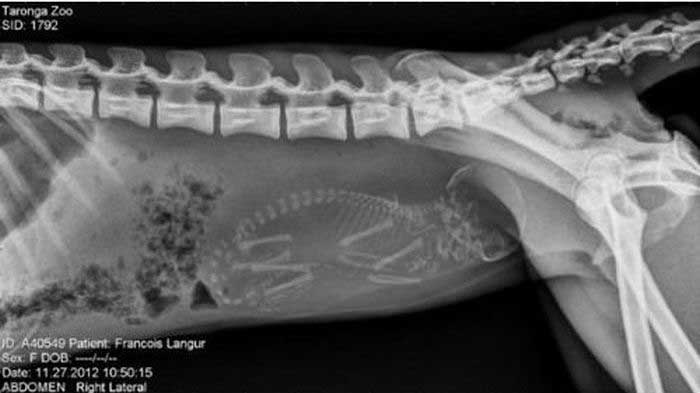

11. サル